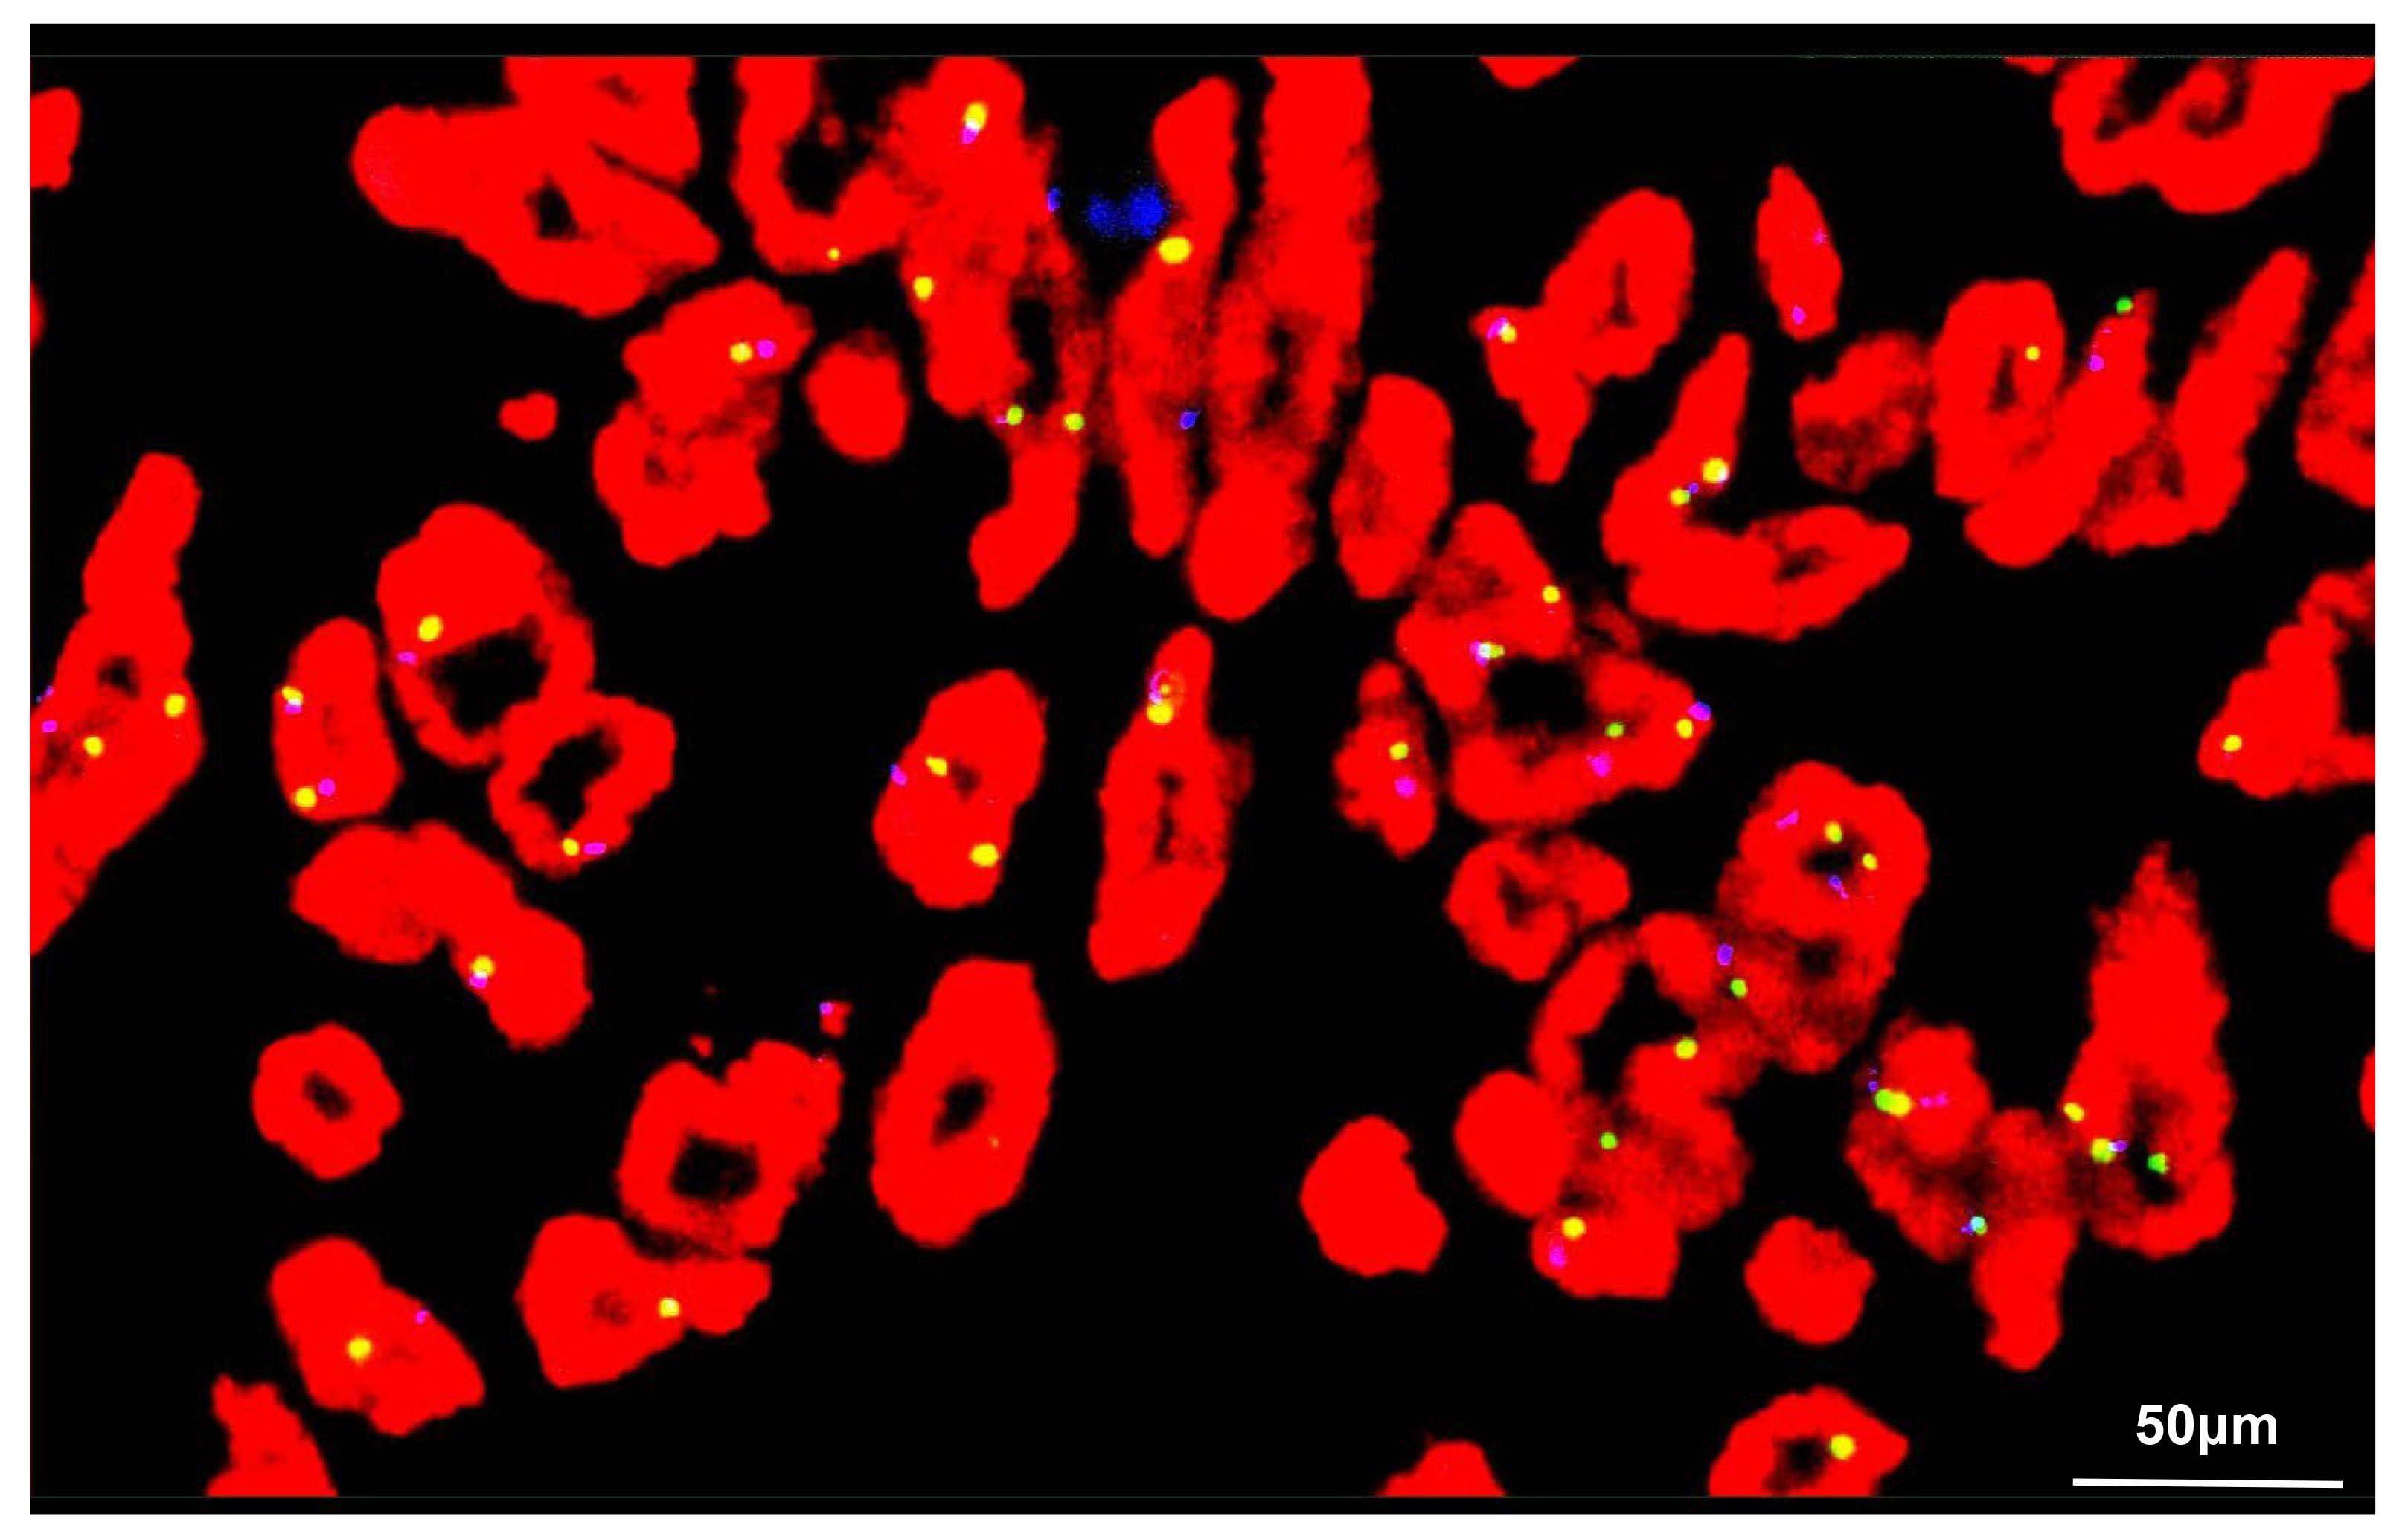

After quenching the endogenous peroxidase activity, tissue slides were incubated with blocking serum and then overnight at 4 °C with primary antibodies against STAT6 (1:50, ab32520, Abcam, Cambridge, Cambridgeshire, UK), CD34 (1:2500, ab81289, Abcam, Cambridge, Cambridgeshire, UK), CD99 (1:250, ab108297, Abcam, Cambridge, Cambridgeshire, UK) and BCL-2 (1:250, ab32124, Abcam, Cambridge, Cambridgeshire, UK). The slides were subsequently incubated with horseradish peroxidase-conjugated secondary antibodies (1:1000, 7074, Cell Signaling Technology, Danvers, MA, USA) for 1 h at room temperature and then photographed with a microscope. The IHC staining results revealed the tumor cells were strongly and diffusely positive for STAT6, CD34, CD99 and BCL-2, but negative for desmin, smooth muscle actin (SMA), human melanoma black 45 (HMB45), and S-100. Mature adipocytes were positive for S-100, and approximately 10% of tumor cells stained positive for Ki-67. Fluorescence in situ hybridization (FISH) analysis was also performed to distinguish the tumor from liposarcoma. Briefly, FISH analysis was performed on the tissue slides following standard protocols and using commercially available probes (F.01017-01, Anbiping, Guangzhou, Guangdong, China) for murine double minute 2 (MDM2, red signal) and a specific probe for centromere 12 (CEP12) as a control (green signal) [44]. A total of 200 interphase nuclei were evaluated in tumor cell-rich areas. The FISH result was negative for amplification of the MDM2 gene in tumor cells (Fig. 5). Based on the above histopathological examination and additional supplementary examinations, a diagnosis of retroperitoneal fat-forming SFT was eventually made.

Fig. 5. FISH analysis of the tumor cells. FISH revealed the total number of MDM2 (red) and CEP12 (green) signals was 193 and 178, respectively. Hence, no amplification of MDM2 was demonstrated in the tumor cells: MDM2/CEP12 = 1.08